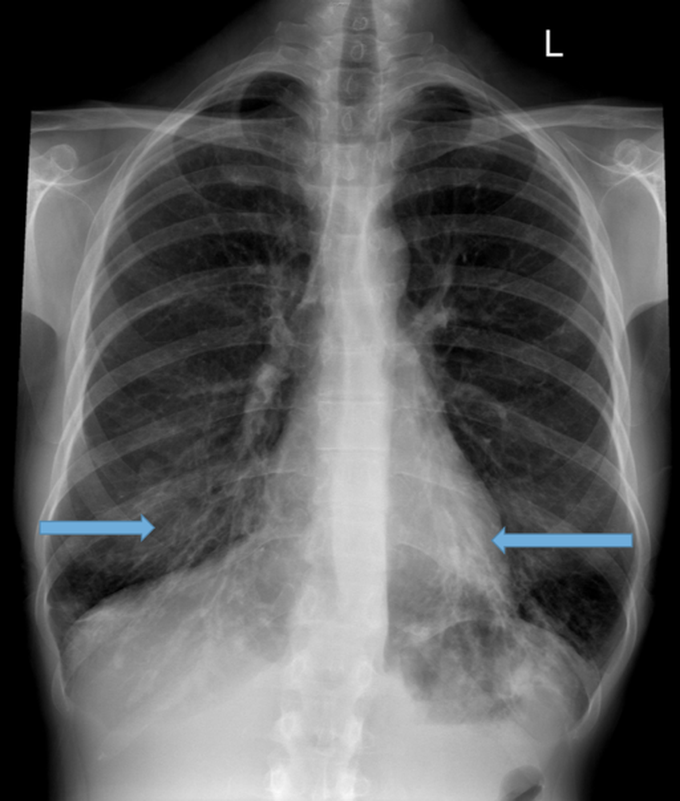

Fig. e X ray chest PA view showing bilateral fluffy opacities and Cotton Wool Appearance Chest X Ray Lateral radiograph of the calvarium in a patient with paget disease reveals multiple patches of sclerotic bone in the calvarium (cotton wool appearance). Radiographers who are able to differentiate alveolar. The blastic, or late inactive,. The cotton wool appearance is a radiographic sign of paget disease, characterized by thickened, disorganized trabeculae and sclerotic patches in bone. This page considers all. Cotton Wool Appearance Chest X Ray.